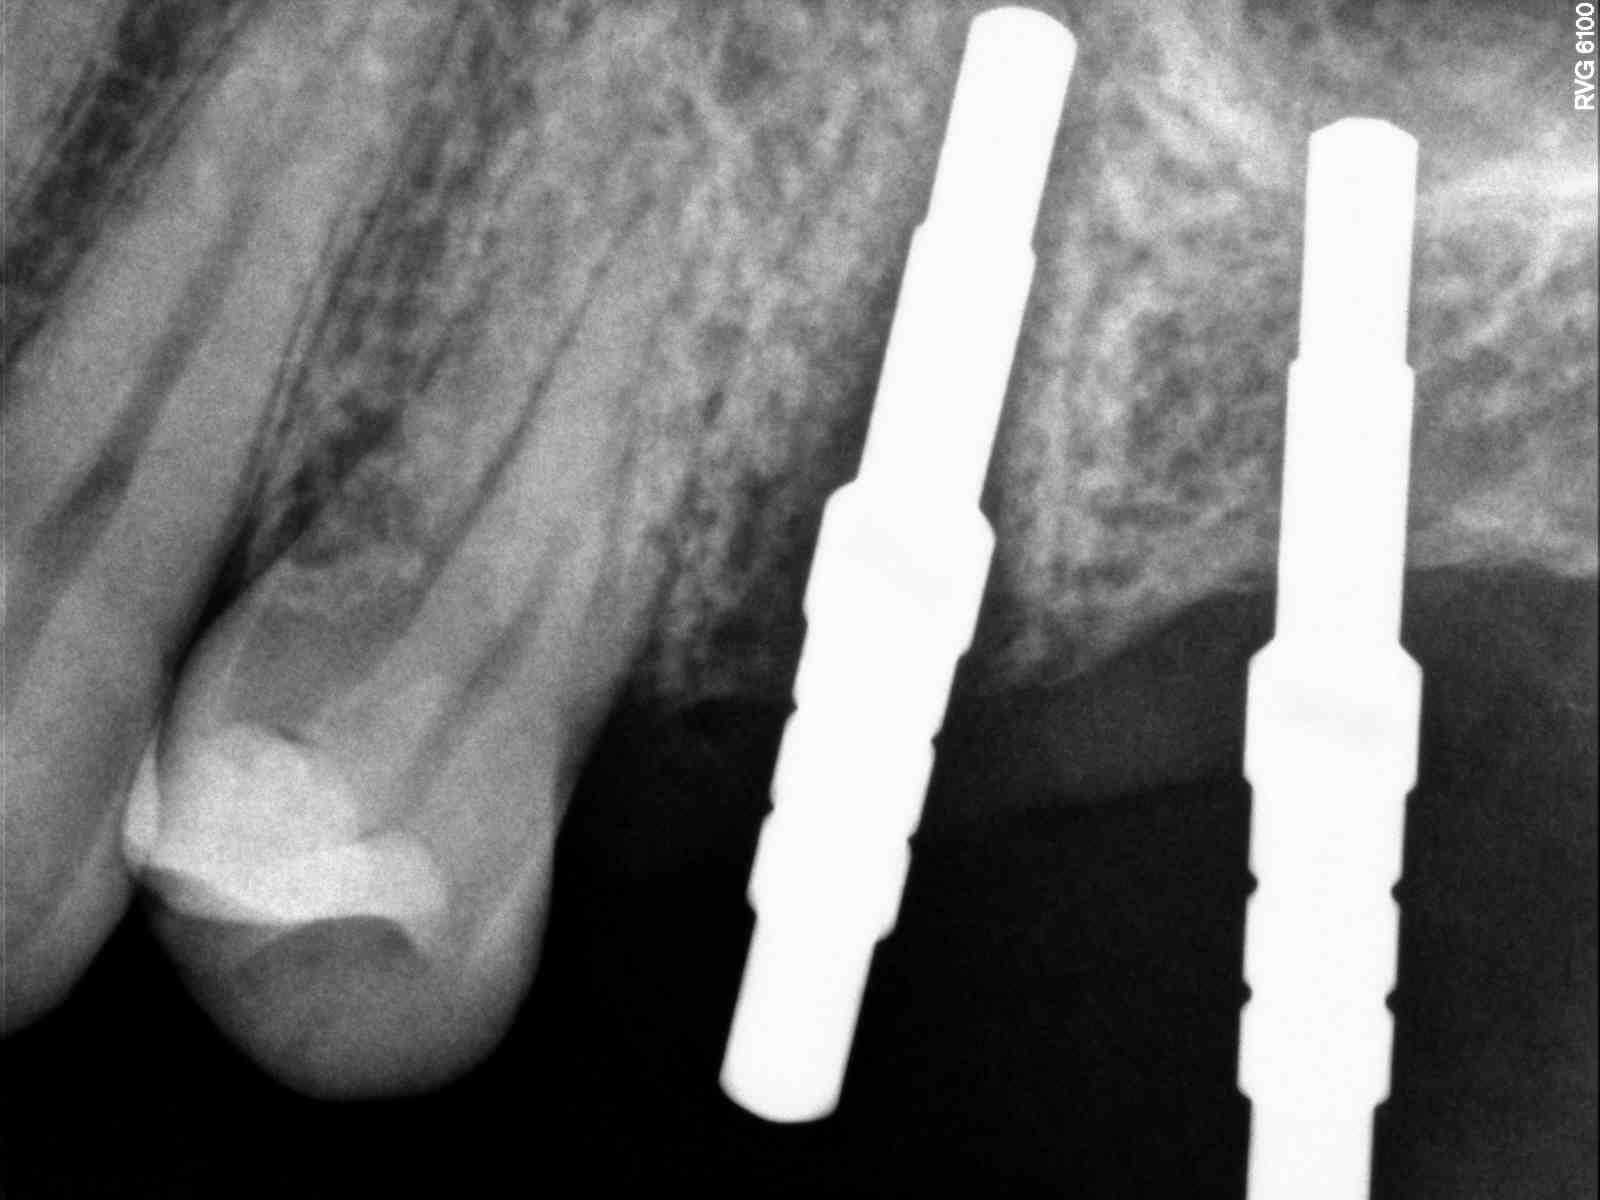

| Checked for sinus perf several times as i know very close |

| Before inserting implant able to visualize completely still in bone |